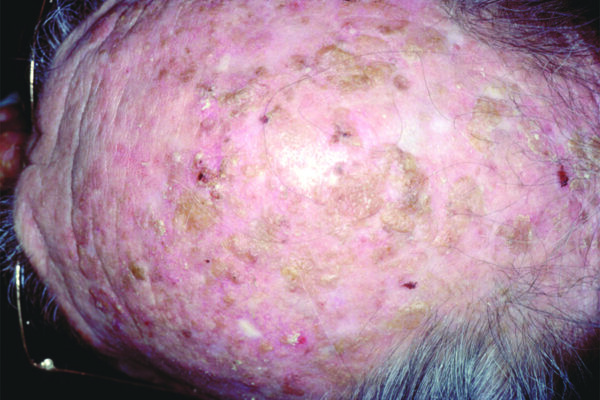

Squamous Cell Carcinoma (SCC) Photos

Squamous cell carcinoma on the head. Photo: International Skin Imaging Collaboration at isic-archive.com

Squamous cell carcinoma on the head. Photo: International Skin Imaging Collaboration at isic-archive.com